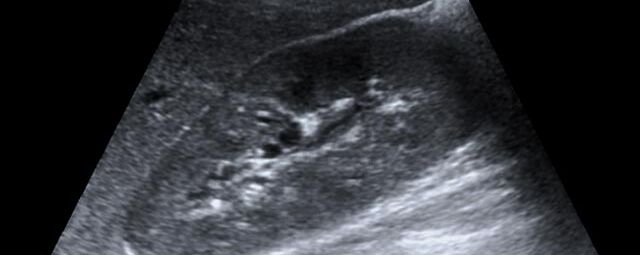

Die Sonographie ist ein bildgebendes Verfahren in der medizinischen Diagnostik, das mit Ultraschallwellen arbeitet. Ultraschall ist Schall mit einer Frequenz oberhalb der menschlichen Hörgrenze. Im medizinischen Bereich werden je nach Körperregion Ultraschallwellen in einem Frequenzbereich von ca. 3,5 – 18 Mhz verwendet. Die körpernahe Ultraschallsonde sendet durch einen piezoelektrischen Effekt kurze Schallwellenimpulse in den Körper. Ultraschall-Gel stellt den Kontakt zwischen Sonde und Körper her. Je nach Gewebeart werden diese Schallwellen im Körper unterschiedlich stark reflektiert. Anhand des zurückgesendeten Schallmusters kann das Ultraschallgerät Schnittbilder berechnen, auf denen die Organe des Körpers nach krankhaften Veränderungen untersucht werden können.

Die Ultraschalluntersuchung ist eine nach derzeitigem medizinischem Kenntnisstand nebenwirkungsfreie Untersuchung. Da bei diesem Verfahren keine Röntgenstrahlung eingesetzt wird, eignet es sich insbesondere bei Kindern, Jugendlichen und jungen Erwachsenen sowie Schwangeren zur initialen Bildgebung. Bei erschwerten Untersuchungsbedingungen (z.B. durch erhöhtes Körpergewicht, Darmluft, Schmerzen oder krankhafte Veränderungen in tiefen Körperegionen, etc.) ist der Ultraschall unter Umständen stark eingeschränkt und muss durch andere Bildgebungen (CT, MRT) ersetzt bzw. ergänzt werden.